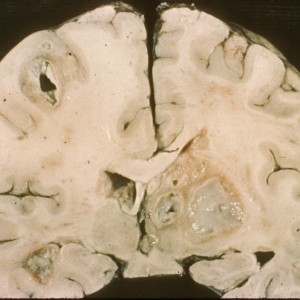

- Causes chorioretinitis (usually bilateral), macrocephaly (due to intrauterine hydrocephalus), seizures, developmental delay, jaundice, hepatosplenomegaly, thrombocytopenia, and purpuric rash.

- MRI with calcifications of the basal ganglia and corticomedullary junction.